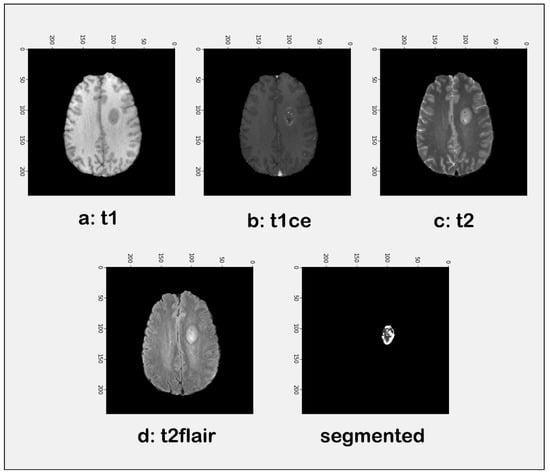

3.2. Tumor Identification

| Modality | Accuracy | Precision | F1 Score |

|---|---|---|---|

| T1 | 94.00 | 93.81 | 95.77 |

| T1ce | 94.00 | 93.81 | 95.77 |

| T2 | 94.38 | 93.62 | 95.65 |

| Flair | 93.23 | 93.81 | 95.77 |

| Segmented | 94.38 | 93.81 | 95.77 |

| Average | 94.20% | 93.77% | 95.75% |